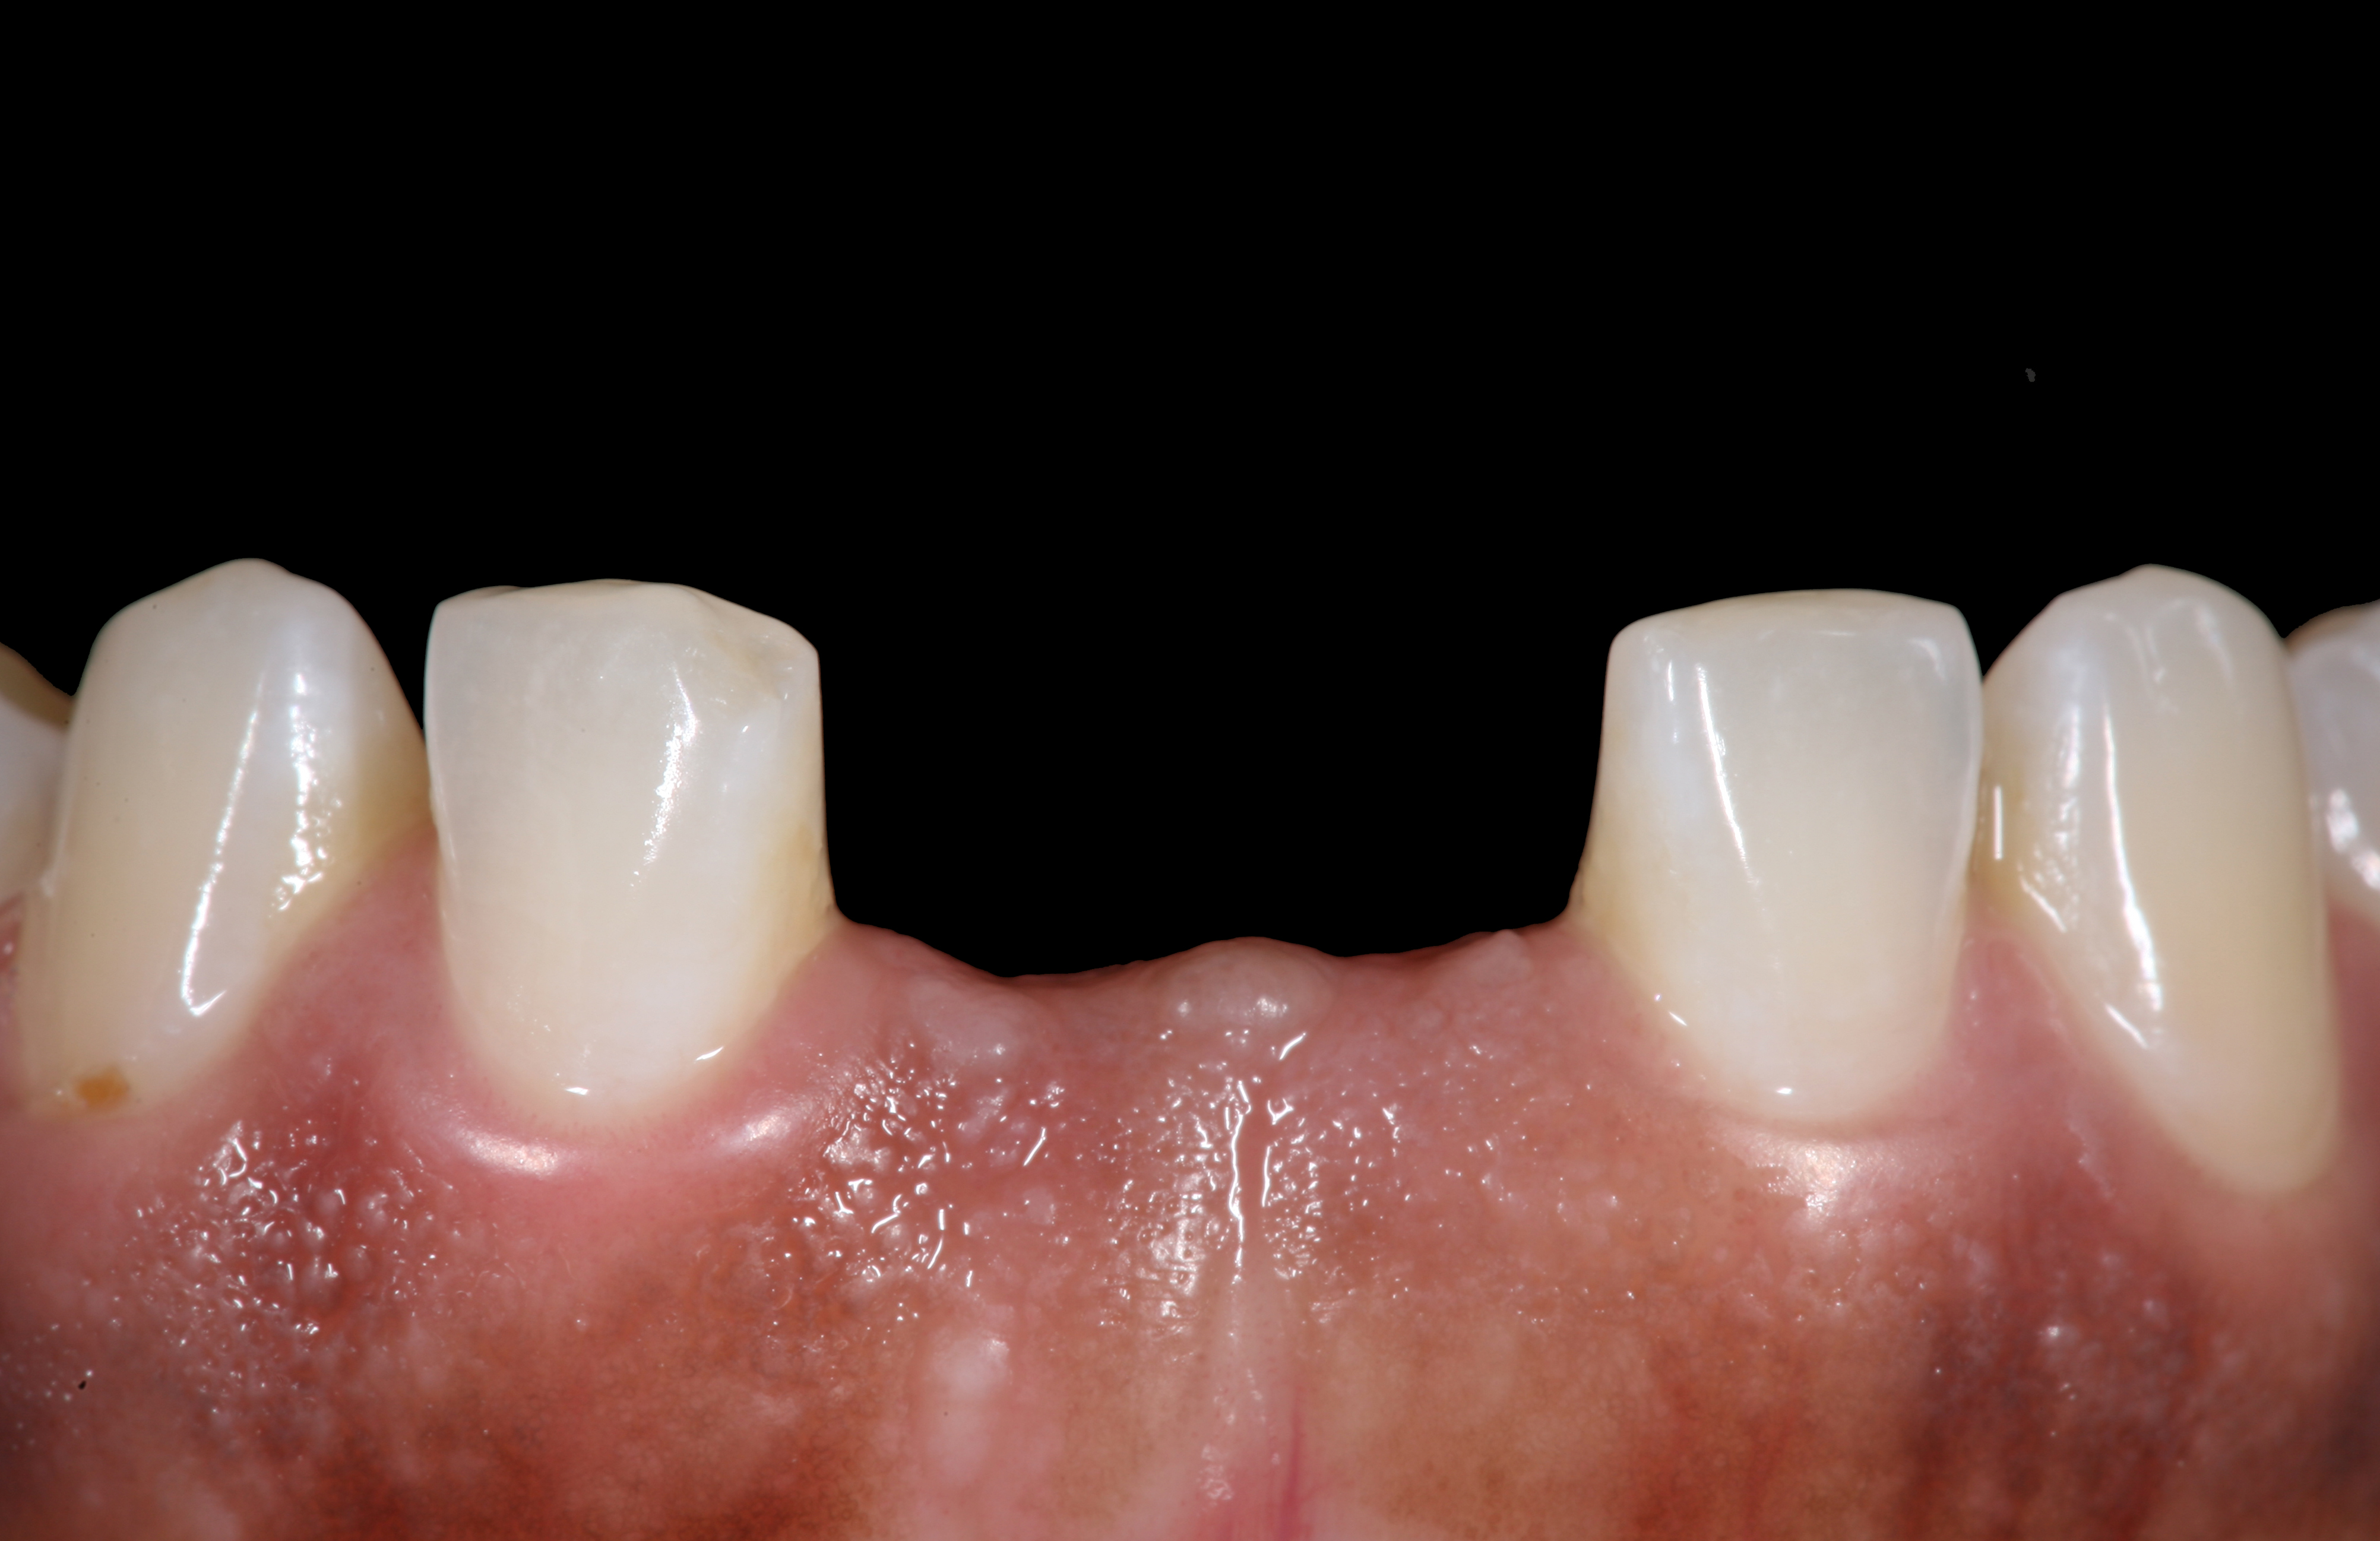

High-strength ceramic materials can be used in select cases to fabricate resin-bonded bridges to replace missing teeth as an alternative to removable prostheses or more invasive procedures such as conventional bridges or dental implants. The two missing lower central incisors (Figure 6) were replaced with two zirconia-based resin-bonded bridges (Figure 7). The single-retainer wing design has shown more than 94% clinical success after 10 years, which is significantly higher than the conventional two-retainer design (67.3% success).6 Proper bonding, however, is key for success and employs an air-particle abrasion step (Figure 8) followed by the application of a special ceramic primer (Figure 9). Figure 10 through Figure 12 demonstrate the clinical outcome.

Figure 6

Figure 7